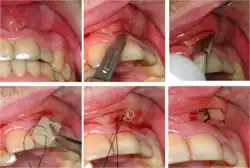

Crown-root fracture with pulp involvement (left). Extracted (right).

Cracked tooth syndrome refers to a highly variable[30] set of pain-sensitivity symptoms that may accompany a tooth fracture, usually sporadic, sharp pain that occurs during biting or with release of biting pressure,[31] or relieved by releasing pressure on the tooth.[10]: 24  The term is falling into disfavor and has given way to the more generalized description of fractures and cracks of the tooth, which allows for the wide variations in signs, symptoms, and prognosis for traumatized teeth. A fracture of a tooth can involve the enamel, dentin, and/or pulp, and can be orientated horizontally or vertically.[10]: 24–25  Fractured or cracked teeth can cause pain via several mechanisms, including dentin hypersensitivity, pulpitis (reversible or irreversible), or periodontal pain. Accordingly, there is no single test or combination of symptoms that accurately diagnose a fracture or crack, although when pain can be stimulated by causing separation of the cusps of the tooth, it's highly suggestive of the disorder.[10]: 27–31  Vertical fractures can be very difficult to identify because the crack can rarely be probed[10]: 27  or seen on radiographs, as the fracture runs in the plane of conventional films (similar to how the split between two adjacent panes of glass is invisible when facing them).[10]: 28–9

When toothache results from dental trauma (regardless of the exact pulpal or periodontal diagnosis), the treatment and prognosis is dependent on the extent of damage to the tooth, the stage of development of the tooth, the degree of displacement or, when the tooth is avulsed, the time out of the socket and the starting health of the tooth and bone. Because of the high variation in treatment and prognosis, dentists often use trauma guides to help determine prognosis and direct treatment decisions.[32][33]

The prognosis for a cracked tooth varies with the extent of the fracture. Those cracks that are irritating the pulp but do not extend through the pulp chamber can be amenable to stabilizing dental restorations such as a crown or composite resin. Should the fracture extend though the pulp chamber and into the root, the prognosis of the tooth is hopeless.[10]: 25